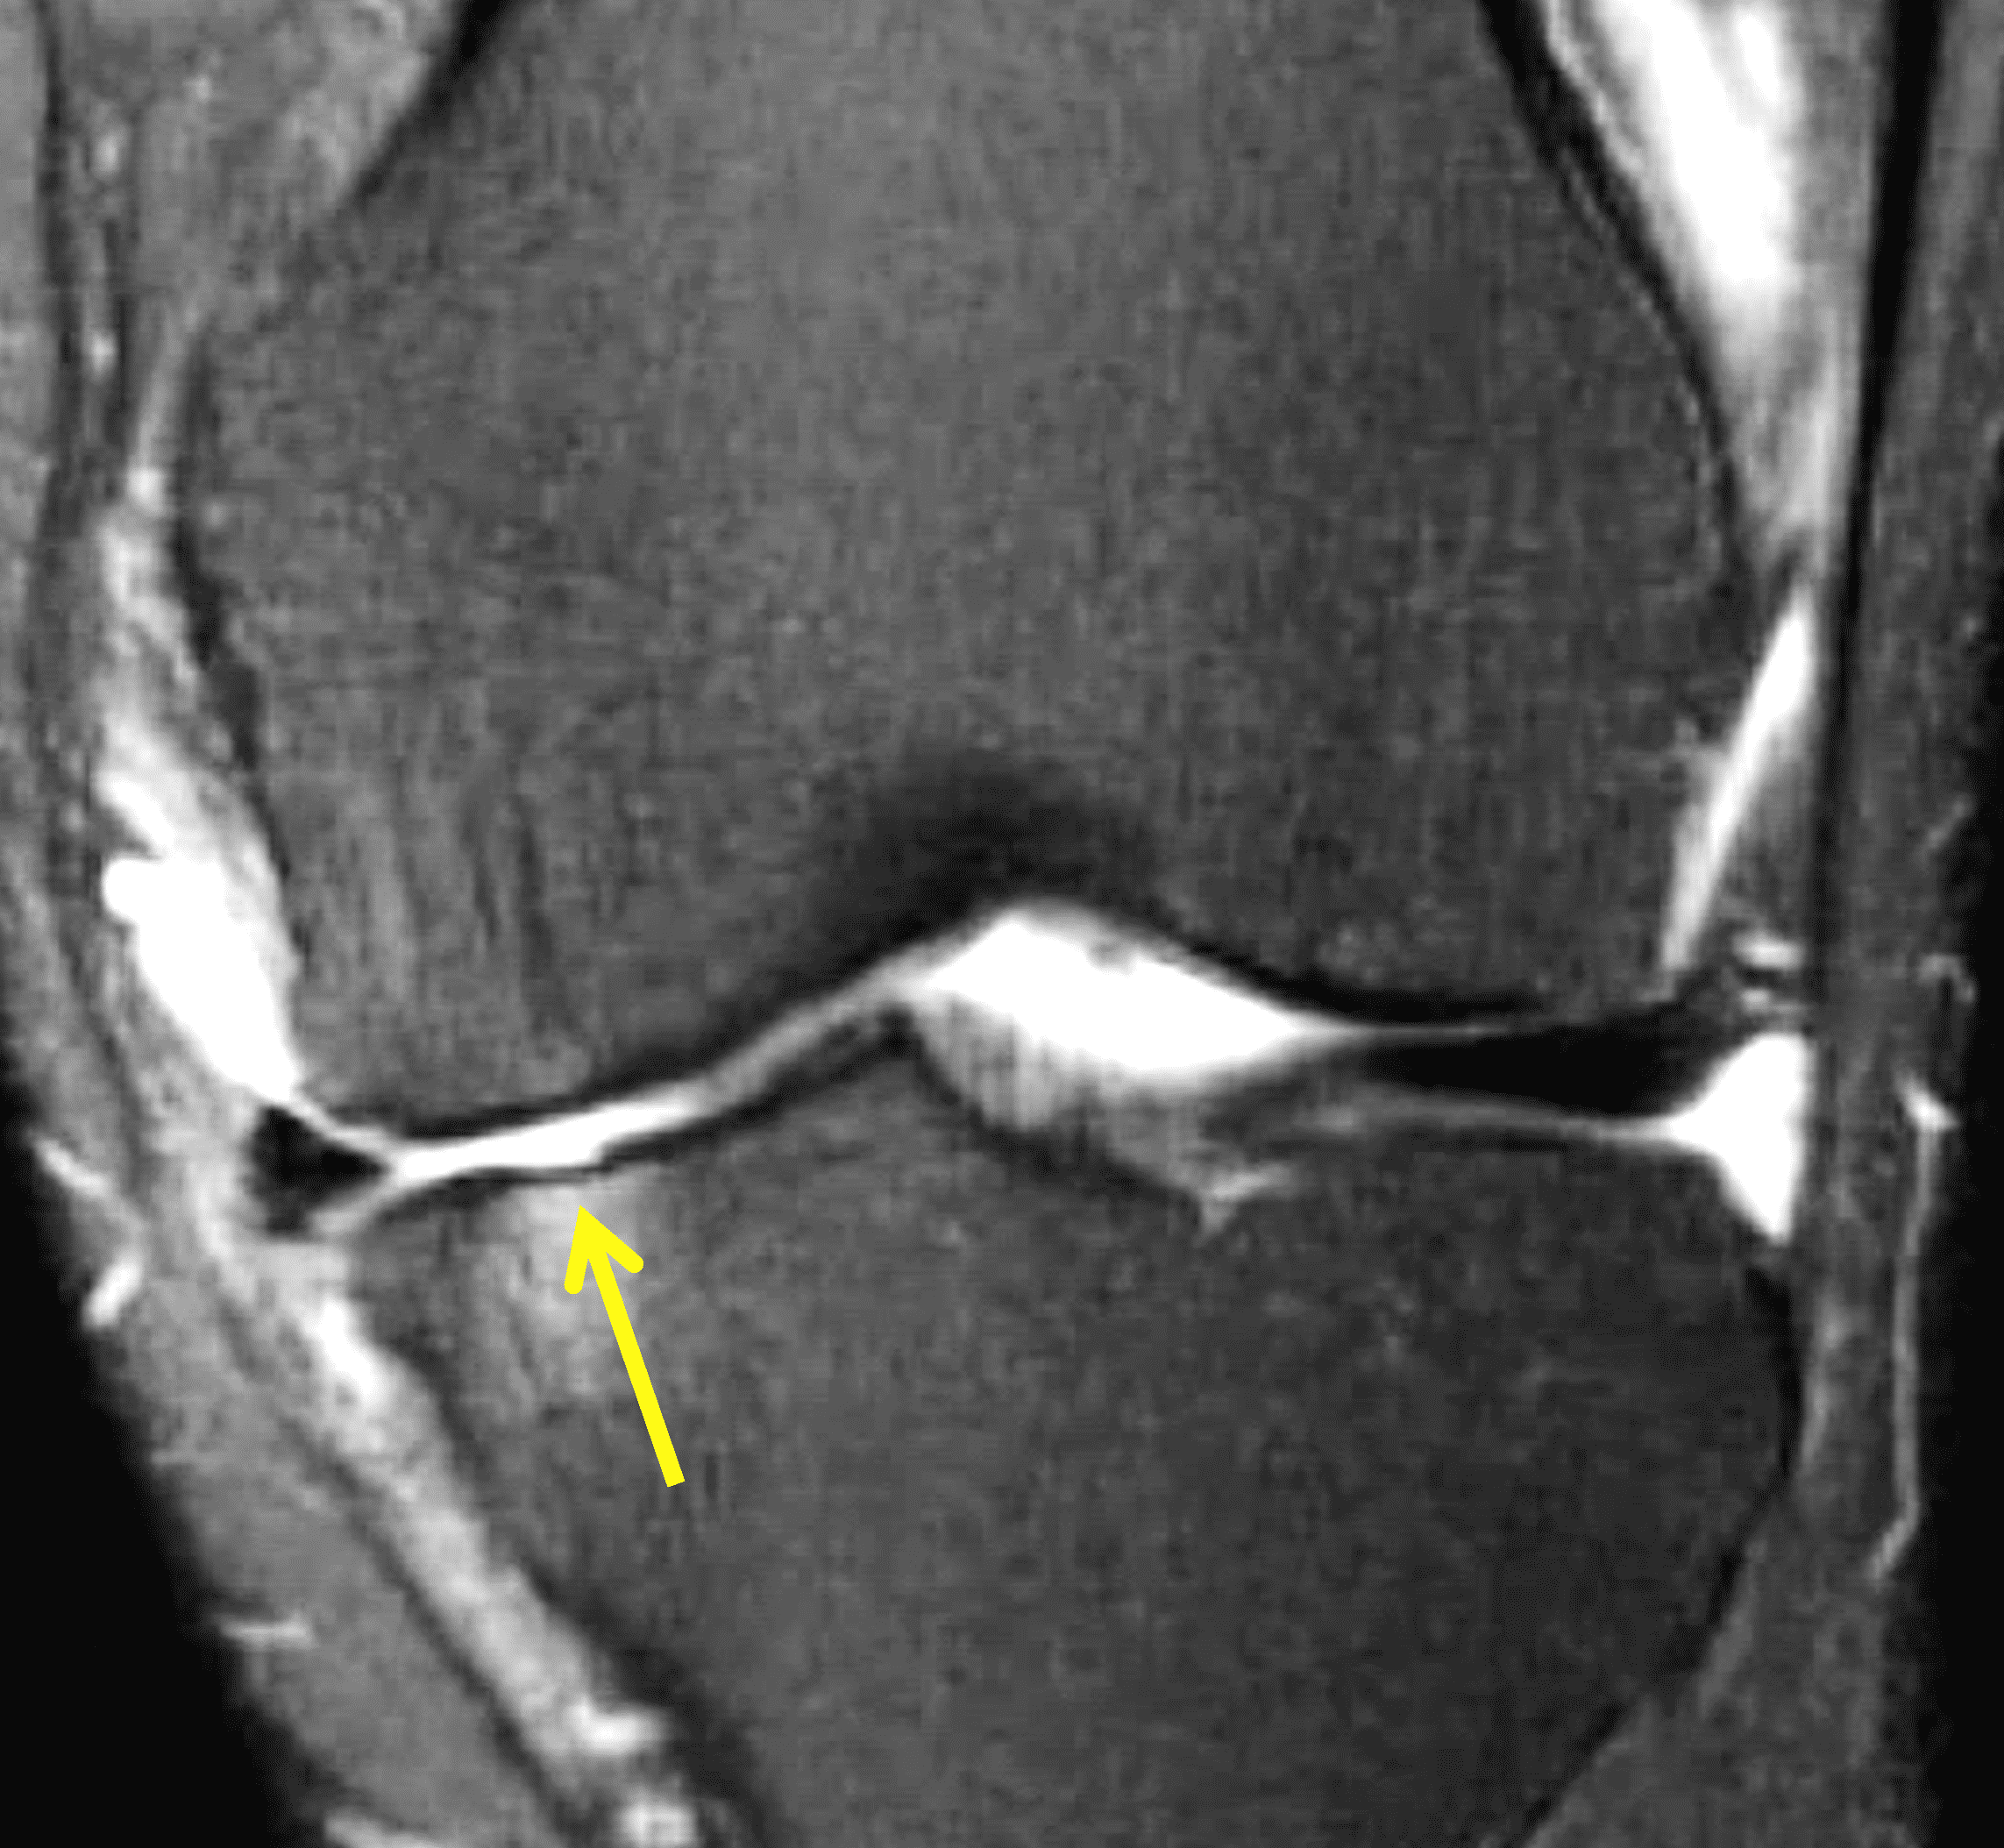

A 32-year-old man suffered a traumatic chondral injury to the medial femoral condyle that was treated with an osteochondral allograft 20 months previously. Representative images from a current knee MRI include (1A) coronal fat-suppressed fluid-sensitive and sagittal (1B) T1-weighted, (1C) proton density-weighted, and (1D) T2-weighted sequences. Are the post-operative MRI findings normal and expected, or abnormal and pathologic? Based on these images, would you characterize the procedure as a success or failure?

Figure 2: (2A) On the coronal image, the margins of the osteochondral graft are faintly visible (arrowheads). Both the graft and underlying bone show mild marrow edema, an expected finding. (2B) The T1-weighted image shows continuity of the marrow in the graft (asterisks) with the underlying bone, indicating osseous integration. A bioabsorbable pin (arrow) used for graft fixation is partly visible. (2C) The proton density-weighted image shows a low signal intensity seam (black arrow) between the native cartilage and transplant, as well as a defect in the subchondral bone plate of the graft (red arrow) where the pin was drilled, both normal findings. (2D) The T2-weighted image shows a smooth, congruent articular surface (arrows), restoring the normal anatomy, and a tiny subchondral cyst. No findings are present to suggest graft failure. The patient’s current symptoms were attributed to pathology elsewhere in the joint (not shown).